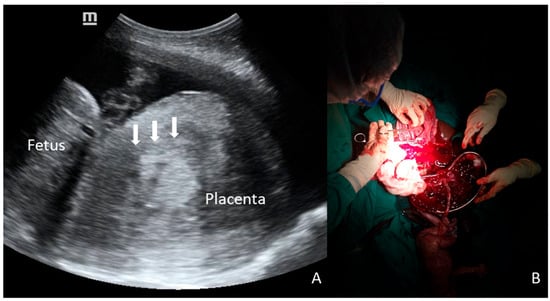

Figure 1.

A 28-year-old primigravid woman at 29 weeks of gestation was admitted with antepartum eclampsia. Fetal heart rate was regular upon admission, but POC-US (A) showed an unusual shape of the placenta, represented by a voluminous, round, inhomogeneous, and Doppler-negative mass, raising suspicion of concealed PA (arrows). Despite the proposal for emergency CS, the patient initially refused surgery, and extensive counseling with her family was required. During this period, fetal surveillance was intermittent due to the unavailability of continuous monitoring. After a delay of several hours, CS was performed, and a massive PA was confirmed; the final outcomes were stillbirth and obstetric hemorrhage (800 mL of retroplacental clots, B).